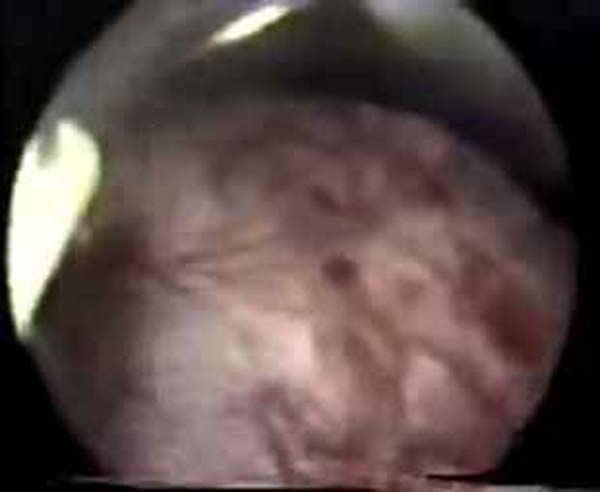

- Hystéroscopie - Hystéroscopie pour l'infertilité

- Clips vidéo de l’hystéroscopie

- Photos de l’hystéroscopie